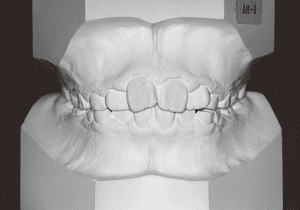

2 After Phase 2 Treatment 6-6-’94

The first phase of treatment involved extracting the left and right maxillary deciduous canines. The space created was used to forcibly retract the four anterior teeth, thereby aiming to improve lip closure function (6–9, 11). Morphological changes suggest that lip function differed before and after treatment (6, 9). Subsequently, the first premolars erupted, but extraction is planned to secure space for canine eruption (10). A Class II molar relationship remains, but the significant overjet has improved (11).

In the maxilla, insufficient space for canine eruption was inevitable, necessitating extraction as part of the treatment plan. The maxillary first premolars on both sides were extracted during routine observation to create space for canine eruption (14). Eventually, the canines erupted and settled into relatively favorable positions (15,19,20). In the mandibular dentition, crowding was also present, leading to extraction of the mandibular first premolars on both sides. Treatment with full bracket was then initiated (17).